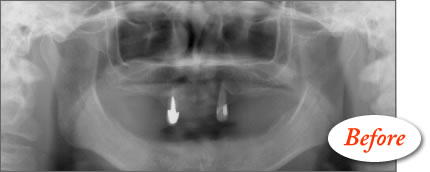

患者さんは48歳(女性)。全顎に義歯が装着されていましたが動かなくて、よく咬めるインプラント治療を希望の為来院。

写真5〜8はそれぞれ術前・後の左側口腔内写真とパノラマレントゲン画像です。

術後のパノラマレントゲン写真では、上顎10本、下顎8本のインプラントが埋入されている事が確認できる。